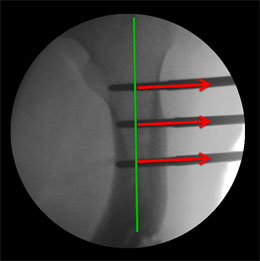

The C-arm picture during surgery, showing the axis of the proximal (upper) segment (green Line) and the red arrows depicting the angle of the Schanz screws applied. The screws are applied perpendicular to each segment, so that when the bone is cut and the screws are made parallel, the axes are aligned in a straight line automatically correcting the deformity. |